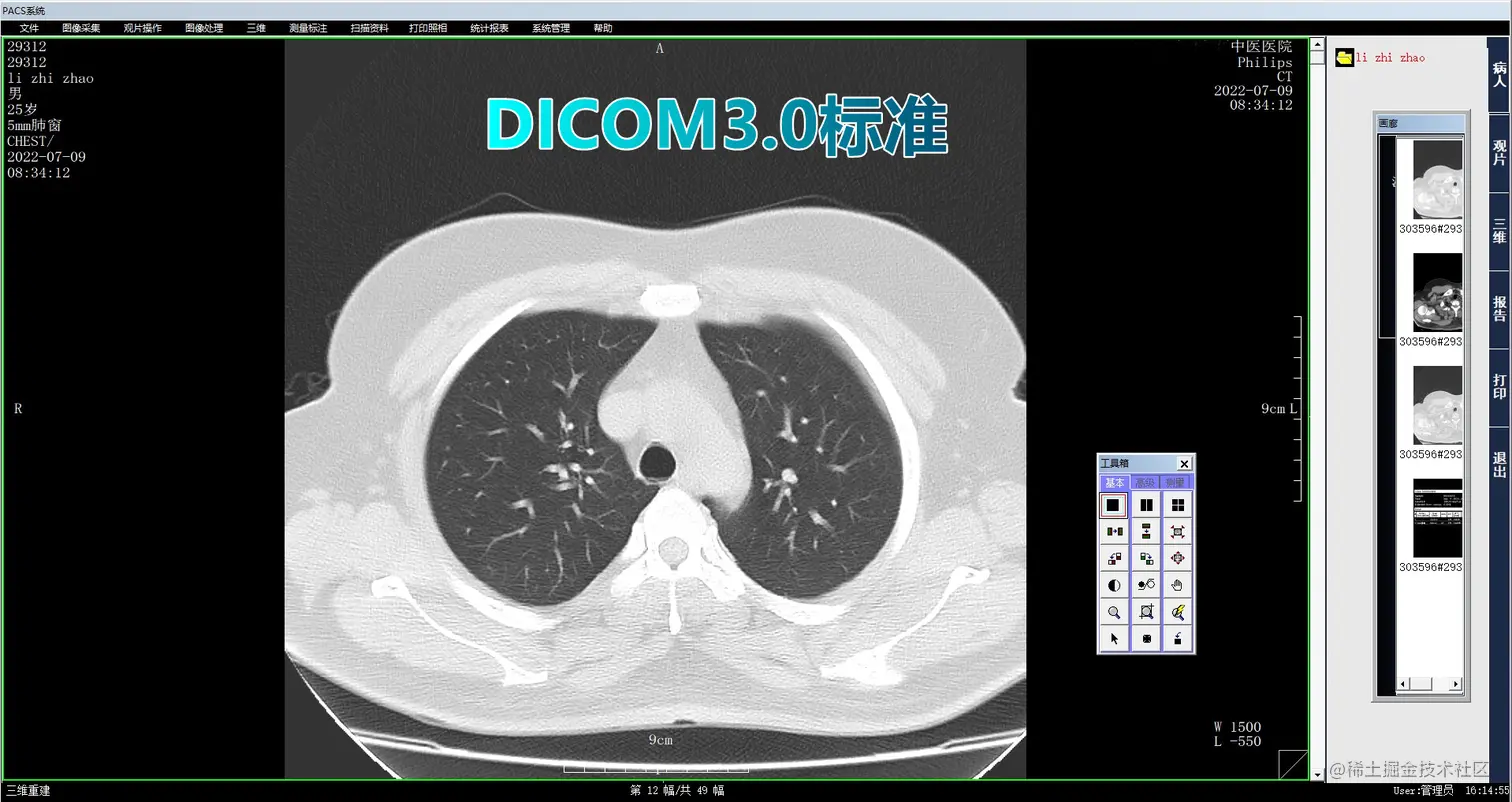

3.计算机阅片:影像医生可以通过系统的计算机阅片功能,快速、方便地浏览患者的影像资料,并进行快速的诊断和处理。系统将自动生成电子报告,并将报告发送给相应的医生和护士。

4_副本.png

医院影像PACS系统是一种重要的影像信息管理系统,可以提高医院影像信息的质量和管理效率,满足医院影像科室的日常工作需要。本文详细介绍了医院影像PACS系统的各项功能,包括检查预约、病人信息登记、计算机阅片、电子报告书写、胶片打印、数据备份等一系列满足影像科室日常工作的功能。未来,我们可以继续探索更多的功能,提高系统的智能化程度,为医院提供更加高效、便捷的服务。